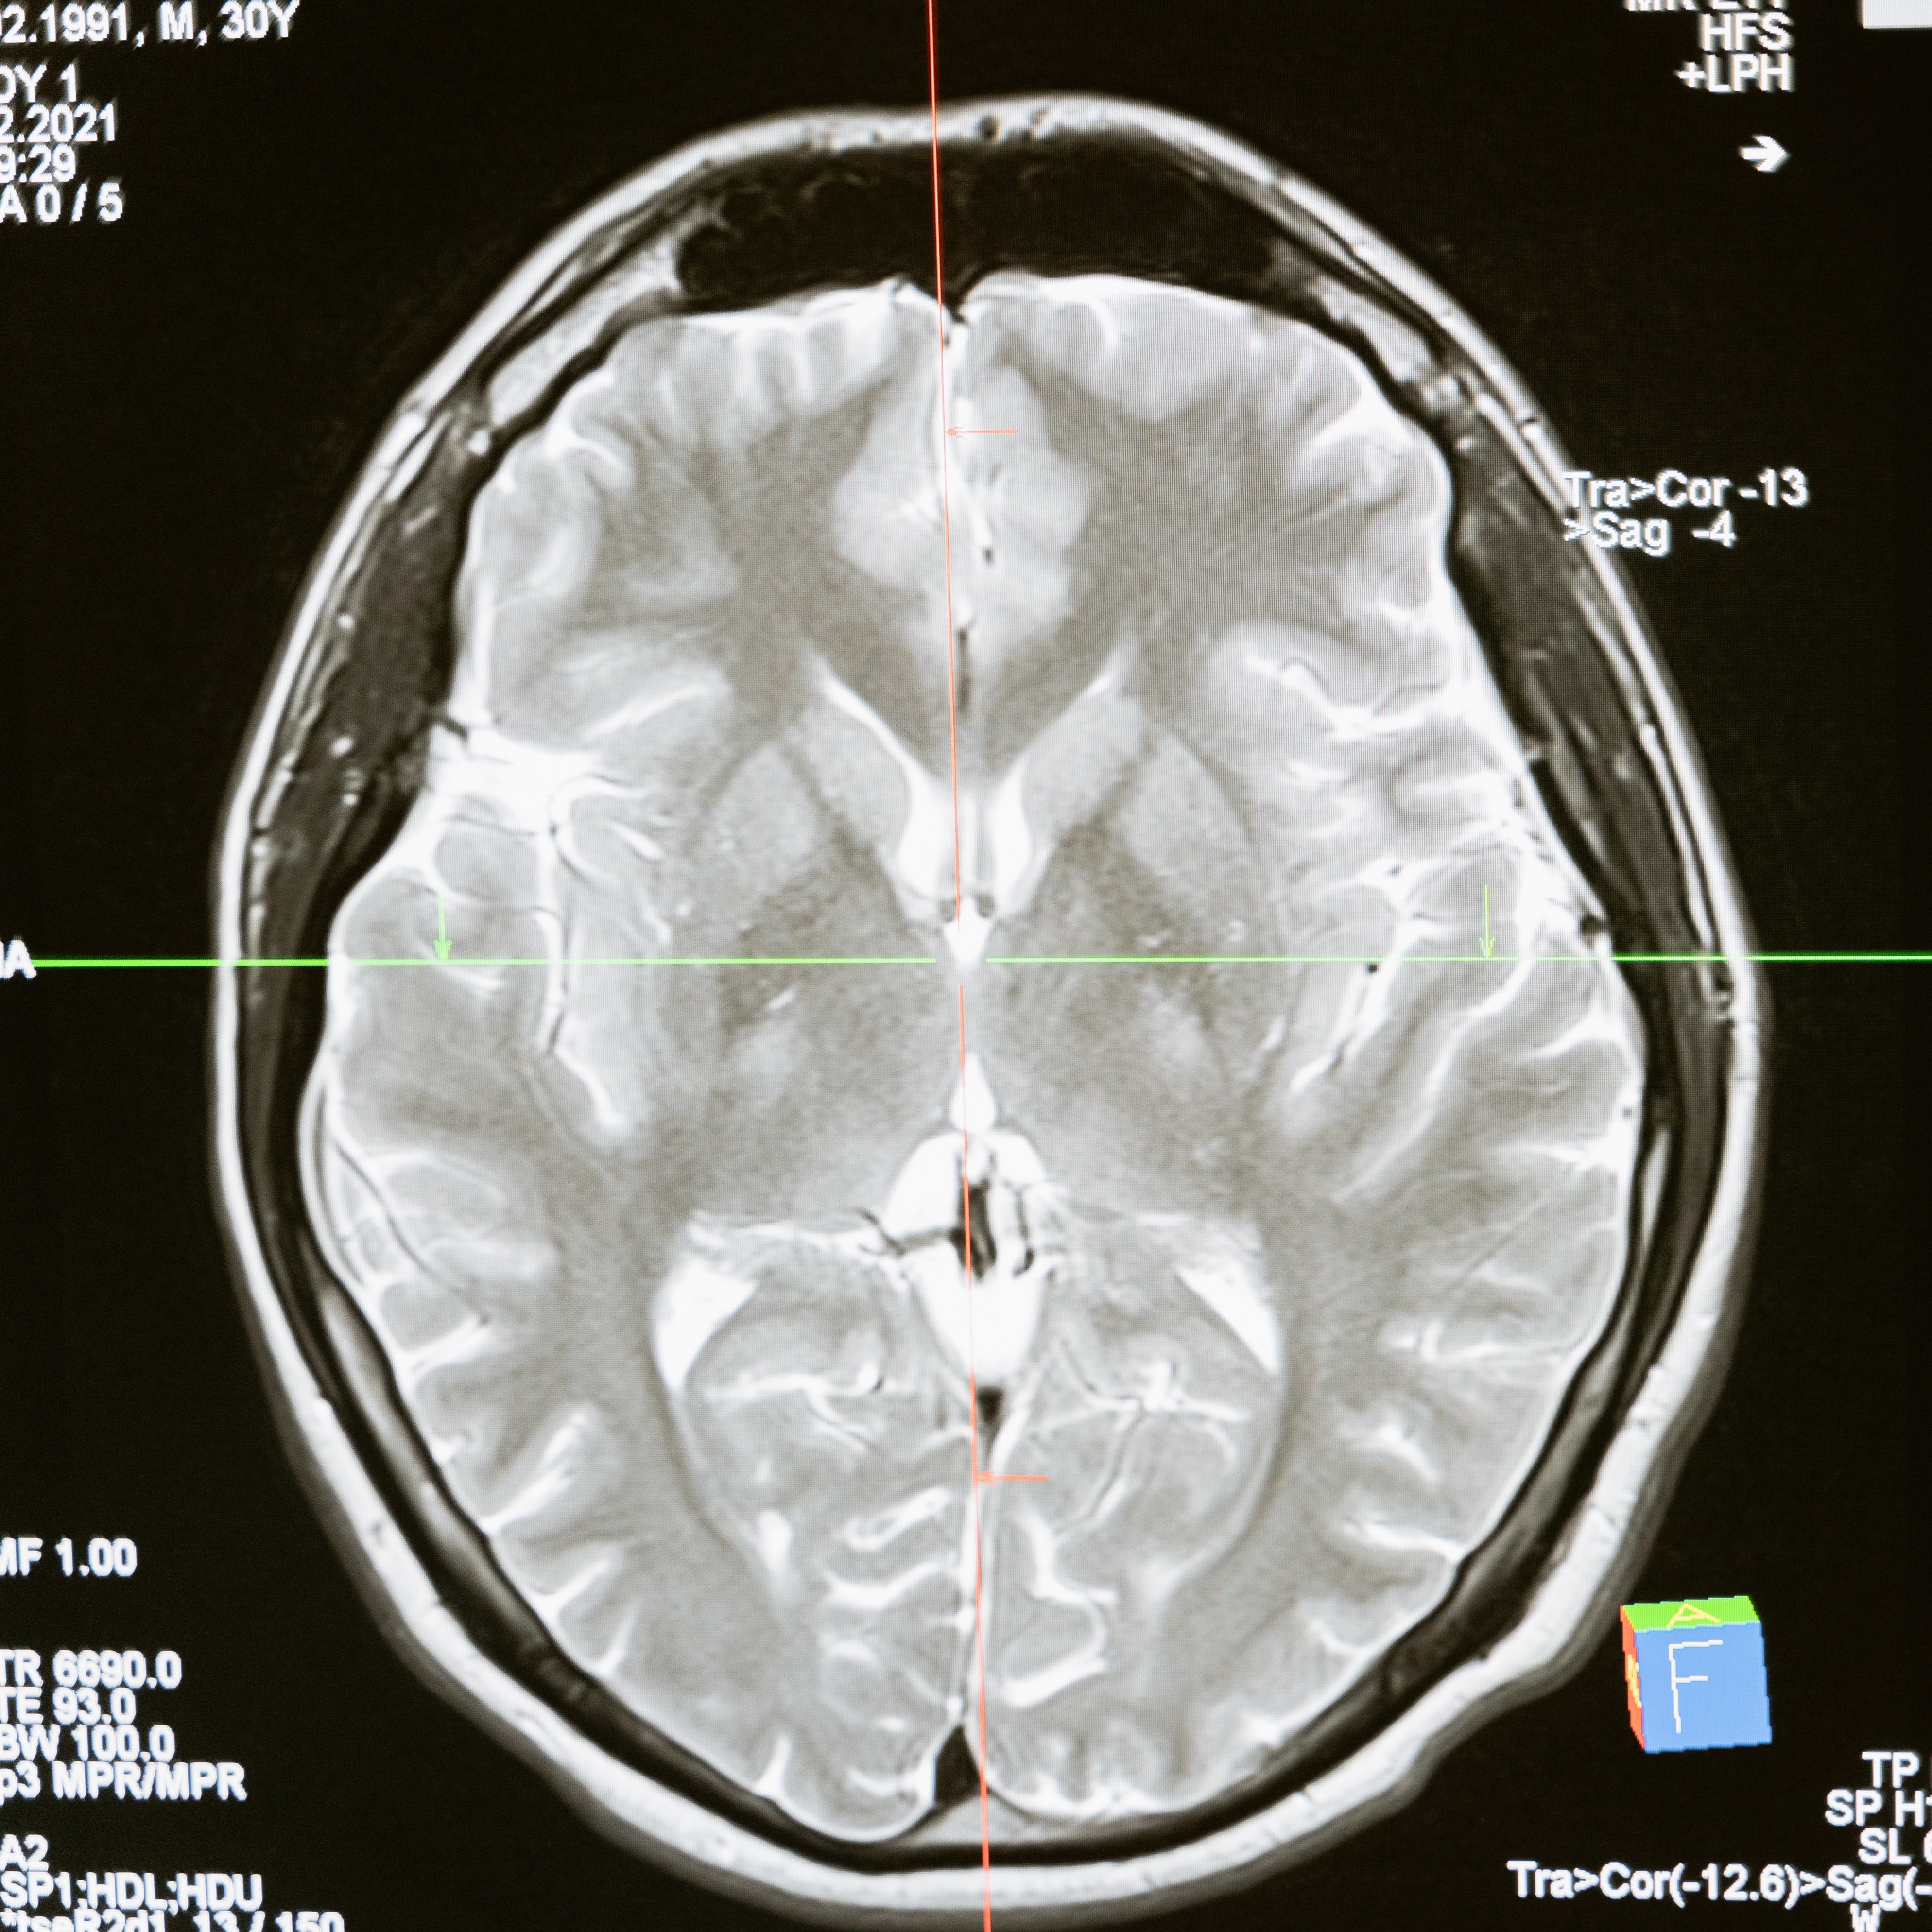

BALANCE is dedicated to building research infrastructure and capacity in collaboration with local and international partners to advance global neurology and health equity research that improves quality of and access to neurological care.